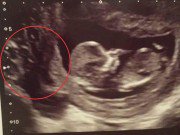

Việc mẹ cần làm khi mang thai tuần 12: Siêu âm đo độ mờ da gáy

Đo độ mờ da gáy hay còn gọi là đo khoảng sáng sau gáy là cách kiểm tra vùng da gáy của thai nhi để phát hiện sớm hội chứng down. Xét nghiệm này thông thường được tiến hành qua phương pháp siêu âm vùng bụng của thai phụ, rất đơn giản, nhanh gọn hoàn toàn không gây nguy hiểm cho mẹ và bé.

Mẹ bầu cần xác định tuổi thai chính xác để thực hiện các giai đoạn thăm khám thai cần thiết trong thai kì. Các chuyên gia sản khoa khuyến cáo, thời điểm thực hiện đo độ mờ da gáy thích hợp nhất từ tuần 11 đến 13 tuần + 6 ngày của thai kì. Tốt nhất là siêu âm vào mốc thai 12 tuần tuổi.

Không thực hiện kiểm tra độ mờ da gáy trước 11 tuần vì bào thai còn quá nhỏ. Còn thực hiện từ 14 tuần trở đi thì kết quả đo không có ý nghĩa nữa vì da gáy có thể trở về bình thường nhưng không có nghĩa thai nhi khỏe mạnh bình thường.

Kết quả đo khoảng sáng sau gáy của thai nhi có thể phối hợp thêm xét nghiệm Double test giúp bác sĩ điều trị cân nhắc về việc bạn có cần thực hiện xét nghiệm tiền sản không xâm lấn (NIPT) hay sinh thiết gai nhai trong giai đoạn này hoặc tiến hành chọc dò nước ối lúc thai 16-17 tuần để truy tìm các các bất thường nhiễm sắc thể ở thai nhi.

Bên cạnh đó, việc siêu âm thai ở tuần 11-13 của thai kì giúp mẹ lần đầu nhìn rõ các bộ phận trên cơ thể của thai nhi như đầu, tay chân, cột sống...